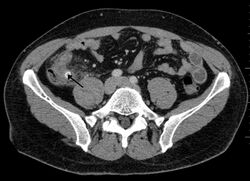

Ultrasound of a normal appendix for comparison

A normal appendix without and with compression. Absence of compressibility indicates appendicitis.[55]